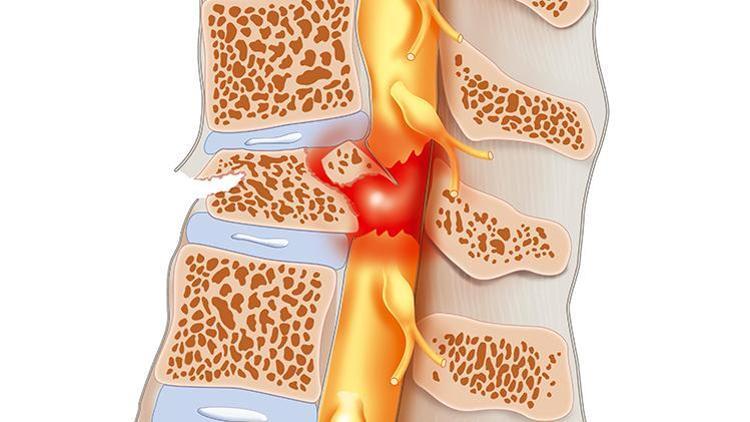

Beyinciğin altından başlayıp kuyruk sokumuna kadar uzanan omurga kanalında bulunan sinir topluluğuna omurilik denir. Bu alandan tüm kaslarımıza ileti gider. Bu yüzden buranın sağlıklı işlevi, sağlığımız için de büyük rol oynuyor. Birçok nedenden dolayı omurilikte hangi bölgede hasar oluşmuşsa o bölgeye sinir iletisi gitmiyor. Bu durumda omurilik felci durumunu ortaya çıkarıyor. Örneğin, sırt bölgesinde bir sorun oluşmuşsa bacaklarda fonksiyon kaybı oluşabilir. Eğer bu hasar boyun bölgesinde ortaya çıkarsa her iki kol ve bacakta işlev kayıpları oluşabilir. Yaralanmanın derecesine göre hastaların iyileşme süreleri de uzayıp kısalabilir.